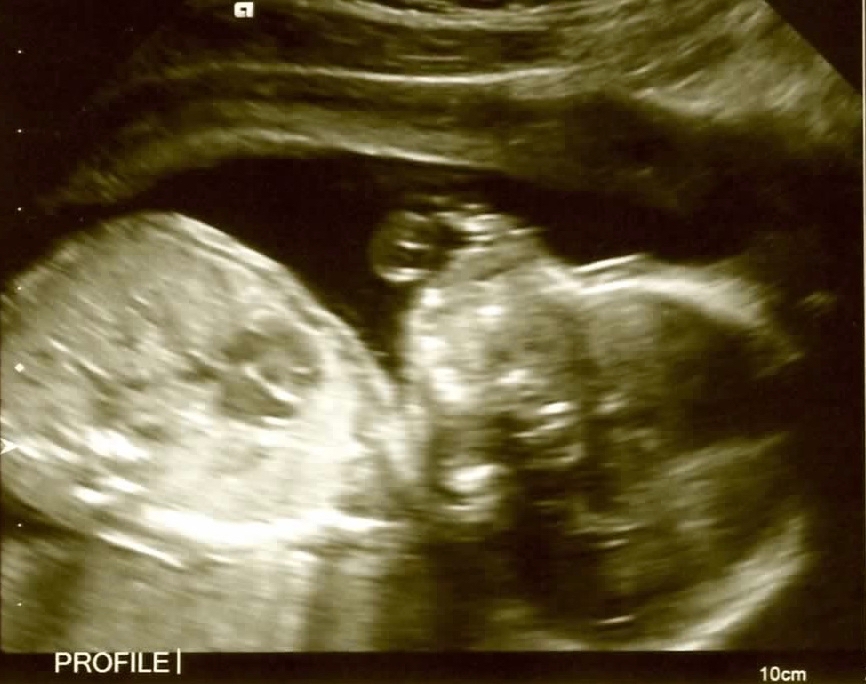

We finally had our scan on Tuesday. We are officially team blue and all is well! Little guy's profile looks just like his brothers did in his ultrasound at 22 weeks. Looks like we might have twins on our hands!

I had my scan today and all looks good! It's definitely a girl, so it was nice to confirm the blood test, though they said they've never had it be wrong for someone. My cyst is still there, but it's smaller, hooray. Didn't get a clear shot of her profile because her hand was in the way, oh well!

All went well for us, baby is tracking a few days ahead and they said everything looks normal. Placenta is anterior which explains me not feeling anything yet. It was weird to see the baby kicking on the screen not feel it! Also, it's a boy!! After the scan I am feeling relieved and way more connected to the pregnancy and ready to actually make plans for him to arrive.

Just had our scan and we have a very active and healthy baby BOY! So relieved because I haven't felt movement yet and am actually down 2 pounds for the overall pregnancy at 19 weeks, but he's actually measuring a few days ahead in size so he's getting what he needs. Celebrating with a huge gooey lemon square and getting ready to finally tell work next week!